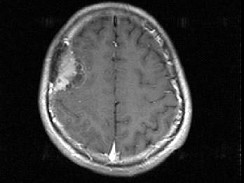

男,48岁,发作性口角抽搐半月,根据所提供图像,最可能的诊断是()

男,48岁,发作性口角抽搐半月,根据所提供图像,最可能的诊断是()

[单选题]男,48岁,发作性口角抽搐半月,根据所提供图像,最可能的诊断是()A . 右额叶胶质瘤B . 右额叶非典型脑膜瘤C . 右额叶骨瘤D . 右额叶炎性肉芽肿E . 右额叶转移瘤

- 查看答案